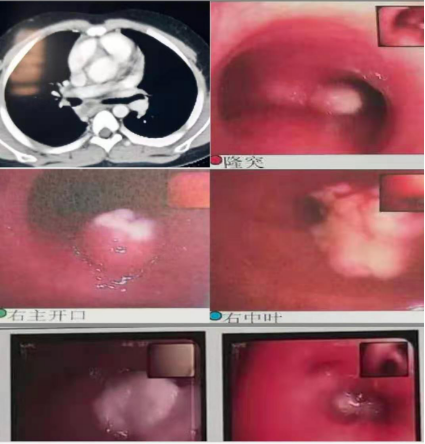

以下为呼吸专业典型病例分享:

图片5:气管内膜结核及重症支原体肺炎所致气道阻塞、塑性支气管束